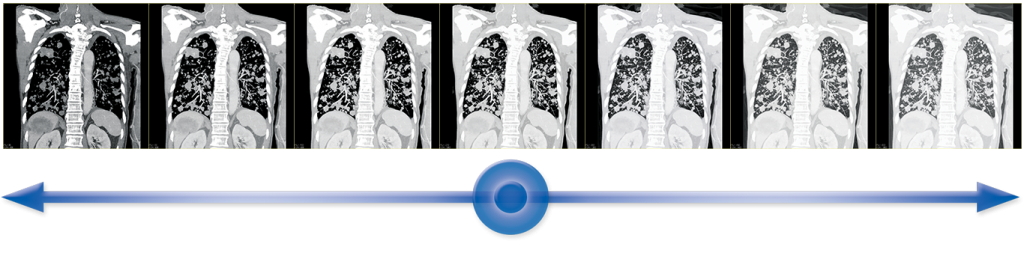

HybridView

Экономия времени и пространства для хранения благодаря гибридным алгоритмам восстановления Toshiba. Эти усовершенствованные алгоритмы реконструкции обеспечивают четкое изображение легких и отличное разрешение мягких тканей на одном изображении. Время чтения сокращается, так как вам нужно сконцентрироваться только на одной серии, чтобы поставить диагноз.